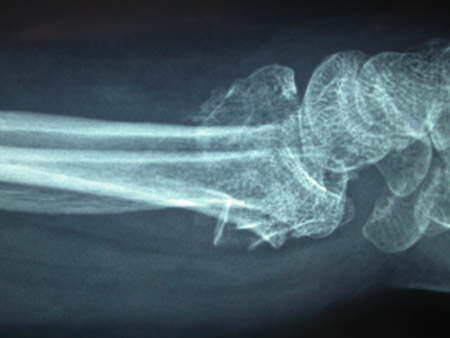

Type C (complex) intra-articular fracture of the distal radius: lateral view

From the collection of Dr Chaitanya S. Mudgal